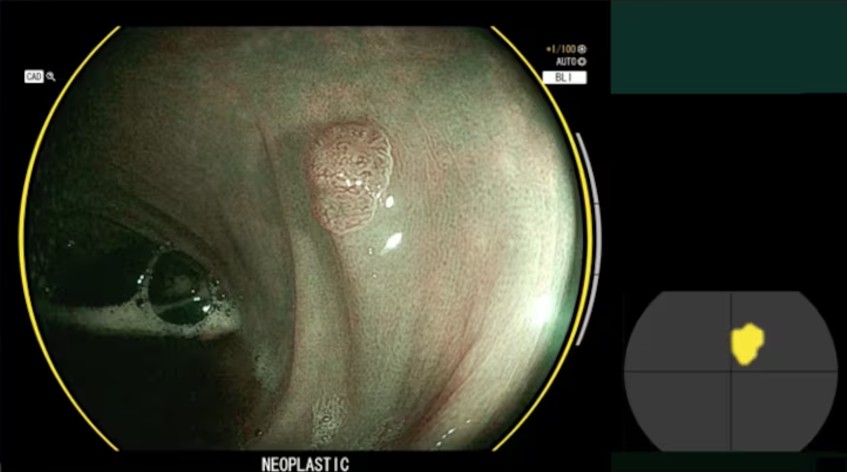

広大な医療の世界では、あらゆる技術の進歩は救われる命を約束します。この分野の最新のヒーローは、CAD-EYE と呼ばれる富士フイルムのイノベーションです。この人工知能 (AI) ツールは単純なソフトウェアではありません。これは、結腸直腸がんの早期発見に不可欠な結腸内視鏡検査の実施方法に真の革新をもたらします。以下では、CAD-EYE について知っておくべきすべてのことと、CAD-EYE が世界中の病院やクリニックでの診断と治療をどのように変えているかを説明します。

キャドアイとは何ですか?

絶対に間違いがなく、病気のわずかな兆候さえも検出できるように訓練された第二の目を想像してみてください。それが **CAD-EYE** です。富士フイルムの内視鏡システムに統合されたこのシステムは、深層学習アルゴリズムを使用して結腸内視鏡検査中の画像を分析します。これらのアルゴリズムは何千もの高解像度ビデオと画像を使用してトレーニングされており、システムがリアルタイムでポリープを認識して分類できるようになります。 CAD-EYE の素晴らしい点は、その精度だけでなく、既存の医療機器にシームレスに統合できるため、病院や診療所での導入が容易であることです。

CAD-EYEの主な機能

1. リアルタイム検出: 結腸内視鏡検査中、CAD-EYE は精力的に動作し、結腸の隅々までポリープをスキャンします。時には非常に小さいか隠れているこれらの地層を検出する能力は、予防医学にとって大きな進歩となります。

2. ポリープの即時特性評価: ポリープが検出されるとすぐに、CAD-EYE が作動してその種類を判別します。良性のポリープと癌性の可能性のあるポリープを区別し、その違いを色で示します。これにより、医師は適切な治療法について、情報に基づいた迅速な決定を下すことができます。

3. 直感的なユーザー インターフェイス: CAD-EYE を使用するのに技術的な専門家である必要はありません。そのインターフェイスはフレンドリーで医療プロセスを補完するように設計されており、ユーザーを圧倒することなく視覚的および聴覚的な支援を提供します。

CAD-EYE を使用する利点

- 精度の向上: CAD-EYE は、特に専門家の疲労が精度に影響を与える長時間にわたる結腸内視鏡検査において、医師が見逃される可能性のあるポリープを検出するのに役立ちます。これは結腸直腸がんの予防にとって非常に重要です。

- 効率の向上: CAD-EYE を使用すると、結腸内視鏡検査の結果を即座に分析できるため、医師は即座に推奨事項を提示できます。これにより、時間が節約されるだけでなく、結果を待つ間の患者の不安も軽減されます。

- ヒューマンエラーの削減: 最も熟練した医師でも悪い日を迎えることがありますが、CAD-EYE ではそうではありません。継続的な監視により、すべてのポリープが確実に検出され、人的ミスのリスクが最小限に抑えられます。

臨床現場での CAD-EYE

結腸直腸がんとの戦いでは、早期発見が鍵となります。 CAD-EYE はこの点で貴重なツールとなっており、医師は癌に発展するずっと前にポリープを検出して特徴づけることができます。既存の機器と統合できる機能と、富士フイルムが医療専門家に提供している継続的なトレーニングにより、システムが効果的かつ安全に使用されることを保証するため、その使用は急速に拡大しています。

CAD-EYEの影響と将来

CAD-EYE のようなテクノロジーの導入は、予防医学がよりアクセスしやすく効果的になる未来に向けた重要な一歩を表しています。個々の処置の結果を改善するだけでなく、世界的に結腸直腸がんの発生率を大幅に減少させる可能性もあります。

CAD-EYE のような AI システムを導入する病院や診療所が増えれば、最終的には命を救う、より迅速で正確な診断による医療の改善が期待できます。これは、テクノロジーと人間のケアを組み合わせて最も困難な病気に取り組む、医学の新時代の始まりにすぎません。

CAD-EYE は単なる技術の進歩ではありません。は、がんとの闘いにおける新たな味方であり、テクノロジーが注意深く正確に適用された場合、医療を変革し、患者の転帰だけでなくすべての人に対する医療の質と効率も向上させる力があることを実証しています。